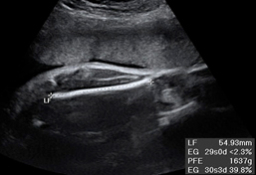

En la ecografía del tercer trimestre es muy difícil extraer una imagen completa del bebé. Rara vez se las apaña el ecografista para poder captar una "foto panorámica" de una criatura, que ya ocupa casi la totalidad del útero materno. Por eso, la mayoría de las ecos de esta edad gestacional se especializan en partes u órganos específicos del feto. El ecografista puede detectar aún ciertas anomalías del desarrollo, comprueba el líquido amniótico, el bienestar fetal y, muy importante, visualiza el cordón umbilical, que puede estar enrollado en algún órgano como cuello, pies o manos.